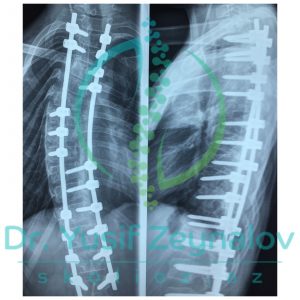

İdiopatik Skoliozlar Səbəbi bəlli olmayan skoliozlardır. Lakin bu skoliotik deformasiyaların yaranma faktorları olduqca çoxdur. İdiopatik skoliozlar zamanı müasir skolioz cərrahiyyəsinin əsasında müasir implantalogiya metodikaları, müasir implantlar, naviqasion sistemlər və 3D modelləşdirmə dayanır. Müasir implantlar və naviqasion sistemlər əvvəllər müalicəsi imkansız hesab edilən ən ağır deformasiyaların belə cərrahi əməliyyatlarını mümkün etmişdir.

-Müasir implantasiya metodikaları və implantlar sayəsində daha kiçik kəsik və daha kiçik onurğa nahiyyəsinin implantasiyası ilə skolioz korreksiyasının aparılması mümkün olmuşdur. Daha az onurğa nahiyyəsində aparılan implantasiya onurğada əməliyyat sonrası hərəkət məhdudluğunun olmamasını təmin edir. Buna baxmayaraq müasir onurğa cərrahiyyəsində onurğanın hərəkətli nahiyələrində əməliyyat zamanı dinamik rodlardan istifadə edirik. Əməliyyat sonrası bir müddət sonra əksər idman növləri ilə məşğul olmaq mümkündür.

-Eyni zamanda müasir skolioz cərrahiyyəsi zamanı 3D modelleşdirmə geniş istifadə edilir. Bele ki, bu metodika vasitasisi ilə oncədən fəqərələrə qoyulacaq implant olçuləri , fəqərə formaları təyin edilir. Öncədən hazırlanmış olçülər hesabına xəstələrədə implantasiya müddəti 2-3 saata enmiş olur. Xəstələrdə əməliyyat zamanı çox hallarda qan transfuziyasına ehtiyac qalmır.

-Skolioz əməliyyatları zamanı sinir və onurğa beyni zədələnmələri və bu fonda mümkün ola biləcək iflic riskinin qarşısını alma məqsədi ilə müasir skolioz cərrahiyyəsində naviqasion və neyromonitarizasion sistemlərdən istifadə edilir. Bu da iflic riskini 0.1%-in altına endirmiş olur.